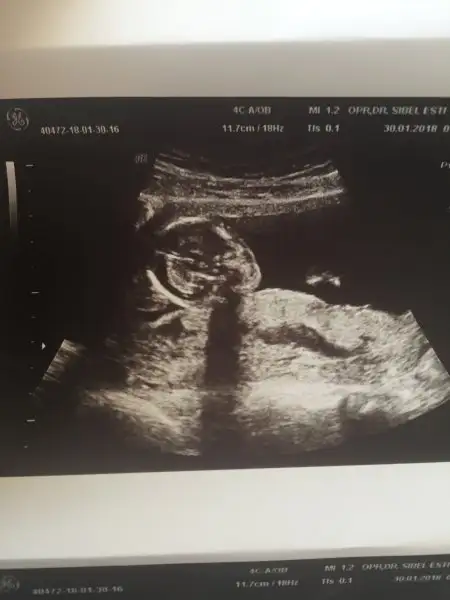

Maşşallah Allahım acılarını göstermesinEki Görüntüle 2103893 Eki Görüntüle 2103894 iste benim pasaaa teyzesi